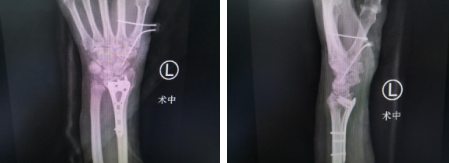

完善各项术前检查后,滕道练医生手术团队为张女士进行了左手腕掌关节脱位复位内固定术,术后可改善拇指稳定性,恢复对捏、対掌功能。术后,张女士对滕医生的技术赞不绝口。

术中